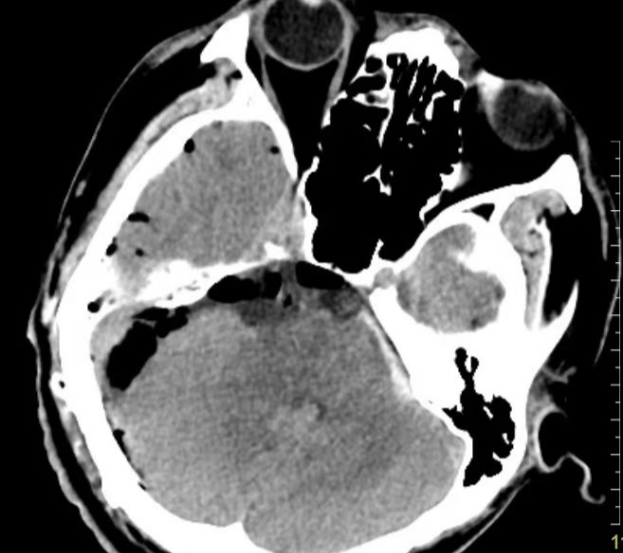

患者李先生(化名),二十多岁,因头晕、听力下降、走路不稳三个月,来到我院神经外科门诊找到郝少才主任就诊。颅脑核磁共振检查结果提示:桥小脑角区竟潜伏着一颗大小超6厘米的巨大肿瘤!这颗肿瘤范围上至鞍上压迫视神经,下至枕骨大孔区,脑干压迫明显且腹侧也有肿瘤生长。肿瘤包绕动眼神经、外展神经、三叉神经、面听神经以及后组多根颅神经,此外也包绕椎基底动脉及其主要分支。

▲术前影像学检查(CT、MRI)